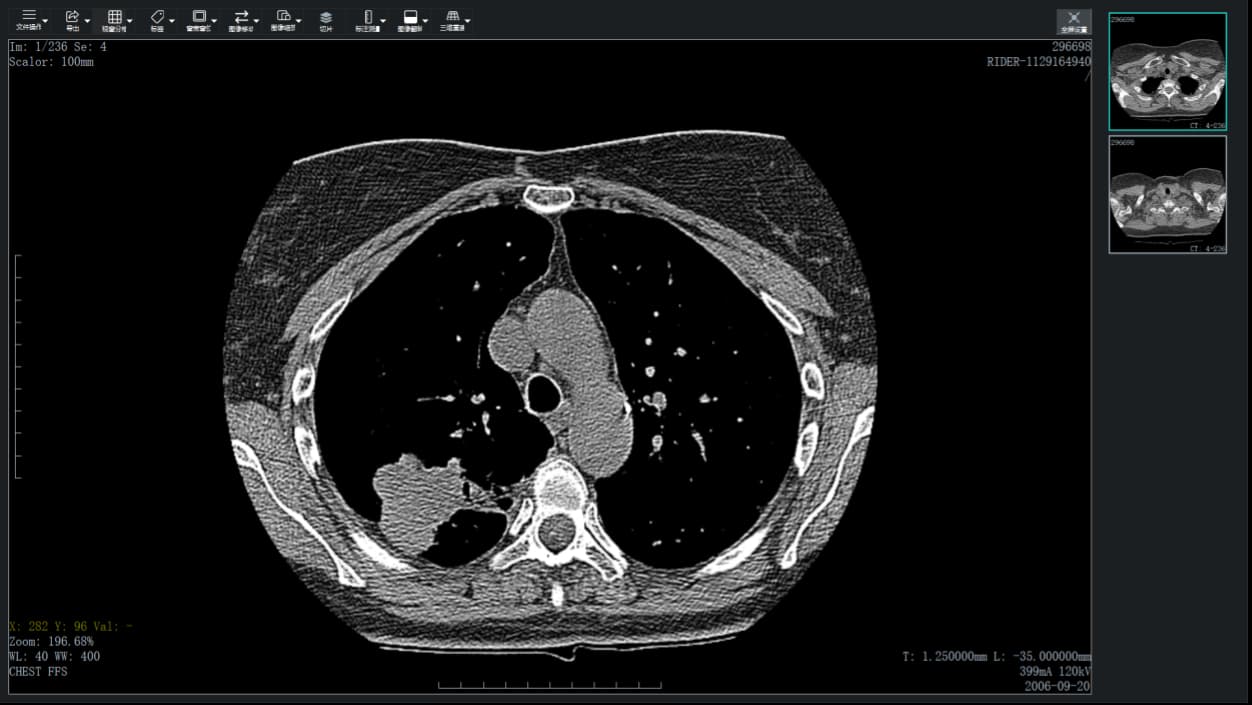

注释DICOM文件包含存储在与图像相关的标签中的大量信息。最重要的数据被覆盖在显示的图像的顶部,分组在角落里:

左上角展示:显示的图像数量和加载的图像总数、序列号、规模大小;

左下角展示:鼠标光标位置(显示的DICOM图像中像素的坐标)和像素值、窗口级别和窗口宽度(亮度和对比度);

右下角展示:切片的厚度和位置(例如CT和MR模式)或x射线灯的旋转和倾斜(XA模式)、患者出生日期。